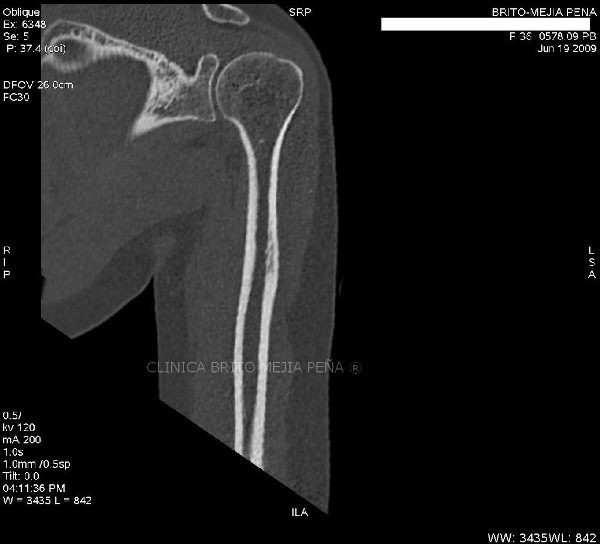

Húmero normal